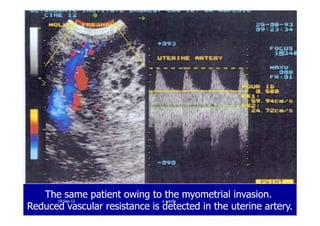

A case of invasive mole: inside the uterine cavity the typicalA case of invasive mole: inside the uterine cavity the typical

““snow stormsnow storm”” appearance can be detected, The location ofappearance can be detected, The location of

blood flow suggest an invasive mole.blood flow suggest an invasive mole.

The same patient owing to the myometrial invasion.The same patient owing to the myometrial invasion.

Reduced vascular resistance is detected in the uterine artery.Reduced vascular resistance is detected in the uterine artery.